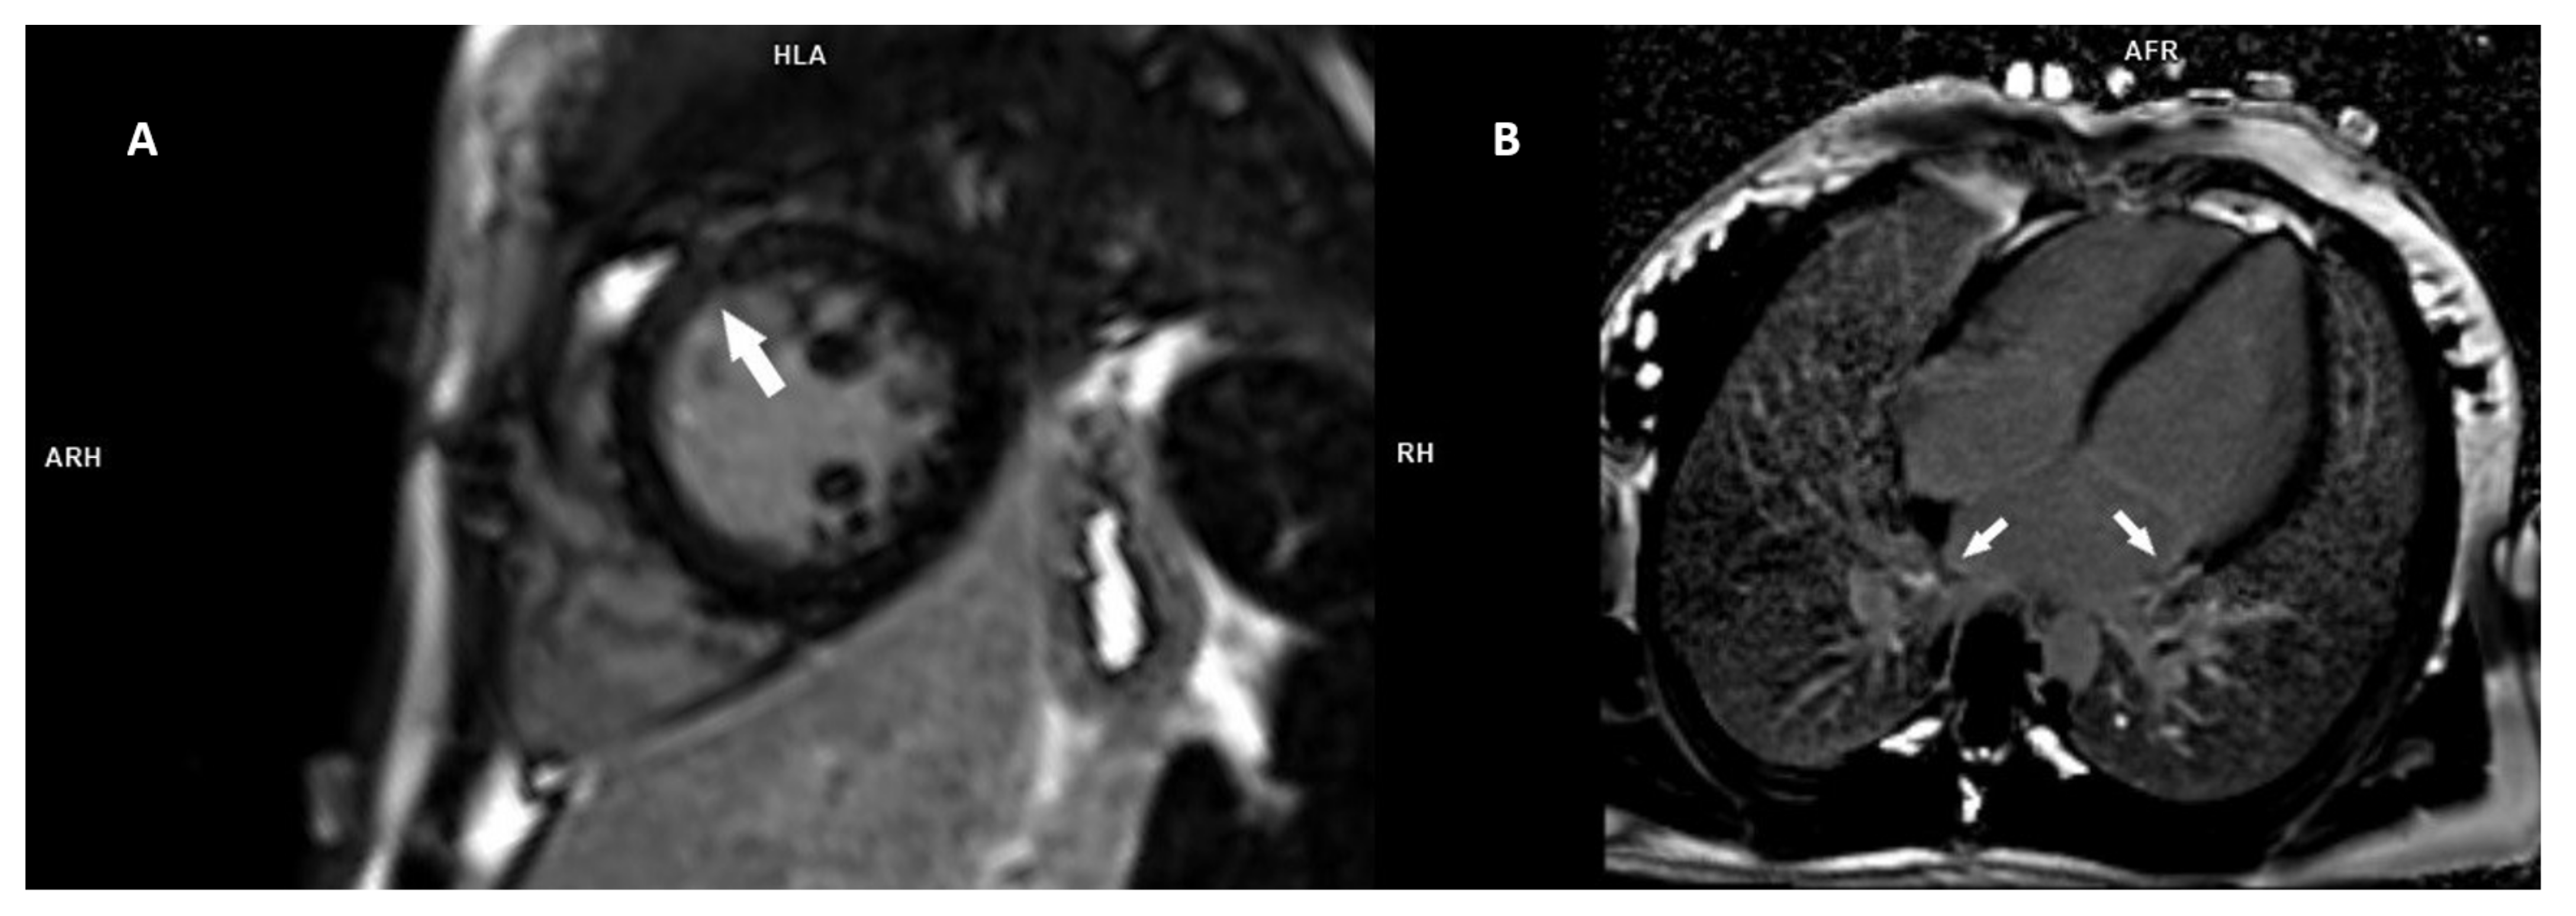

3.1. Family 1

3.2. Family 2

3.3. Family 3

3.4. Family 4